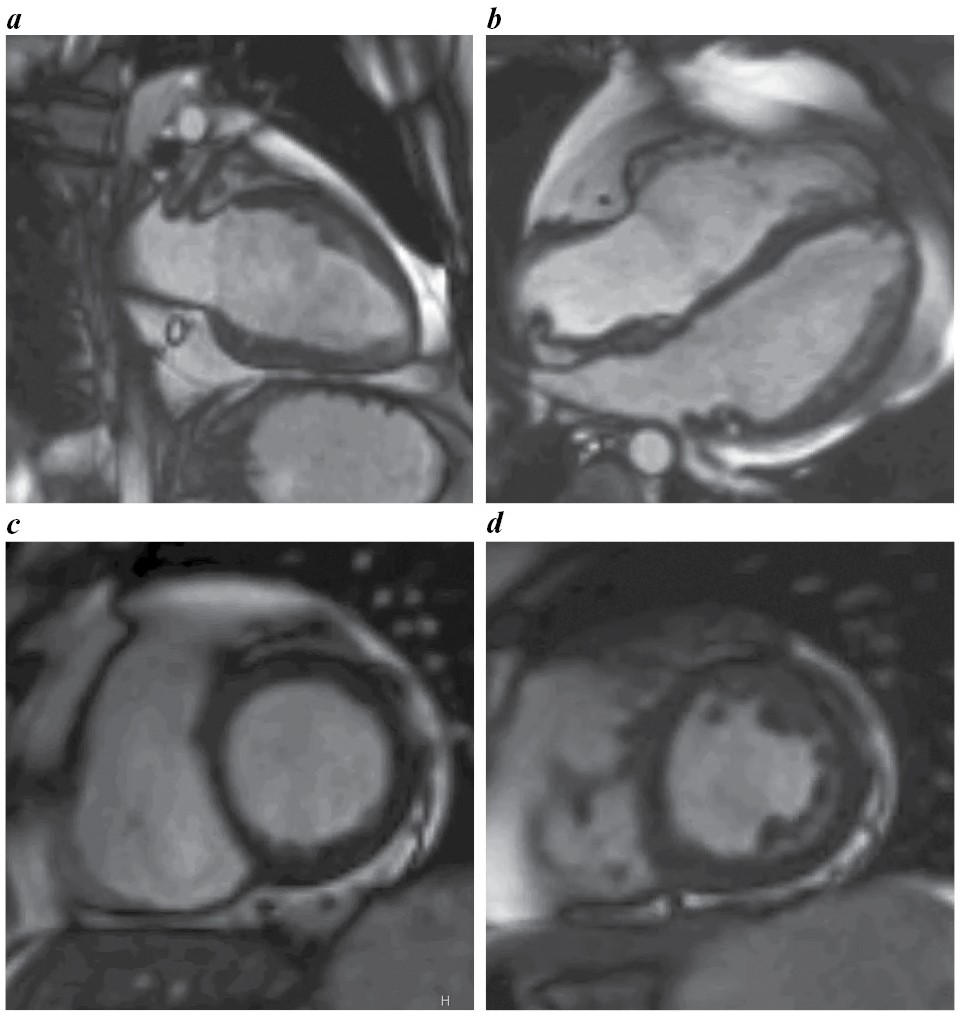

Выполнена магнитно-резонансная томография (МРТ) сердца с контрастированием (рис. 3, a–d), по данным которой очагового поражения миокарда желудочков воспалительного или ишемического характера, признаков отека миокарда и зон фиброза не выявлено. Не обнаружено расширения полостей ЛЖ и ПЖ (индексированный конечный диастолический объем ЛЖ – 60,4 мл/м2, индексированный конечный диастолический объем ПЖ – 47,9 мл/м2). Сократимость ПЖ оставалась в пределах нормы, ЛЖ незначительно снижена – до 54%. Толщина миокарда ЛЖ и ПЖ – в пределах нормы. Визуализировалась трабекулярность боковой стенки ЛЖ, не достигающая критериев некомпактного миокарда (рис. 4, a–d). В полости перикарда не выявлено жидкости, однако обращали внимание скопление эпикардиальной жировой ткани (более 200 г) на уровне атриовентрикулярных борозд, вдоль обоих желудочков, толщиной до 2,3–2,4 см (рис. 5, a–d), также липоматоз межпредсердной перегородки (рис. 5, b), скопление жировой ткани паракардиально (более 100 г).

Рис. 4. МРТ сердца с отсроченным контрастированием: a – 2-камерная длинная ось ЛЖ; b – 4-камерная длинная ось ЛЖ; c, d – короткая ось ЛЖ через базальный и средний сегменты. Патологическое контрастирование миокарда ЛЖ и ПЖ отсутствует.

Fig. 4. Cardiac MRI with delayed contrast enhancement: a – 2-chamber long axis of the LV; b – 4-chamber long axis of the LV; c, d – short axis of the LV through the basal and middle segments. No abnormal contrast uptake of the LV and RV myocardium.